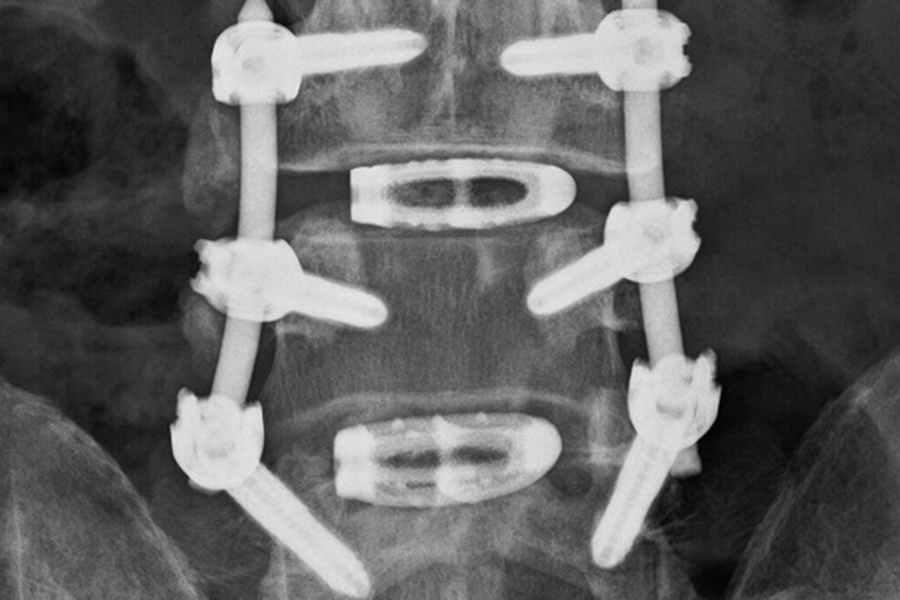

Nach Operation und Stabilisierung eines Wirbelgleitens und einer Verengung des Spinalkanals.

Nach Operation und Stabilisierung eines Wirbelgleitens und einer Verengung des Spinalkanals